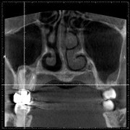

CTやレントゲンを使った徹底的な検査・診断・チェック

根管治療では、マイクロスコープや拡大鏡を使うことにより肉眼では見づらい根管をはっきり見ることができます。

しかし、複雑な歯の根の中を治療するには、それらだけでは万全ではありません。

当院では、CTやレントゲンを使って目に見えない部分の問題やポイントも見逃しません。

CTやレントゲンのデータは、治療前の徹底的な検査や診断に役立てるほか、治療後のチェックにも使用されます。

CT画像の例